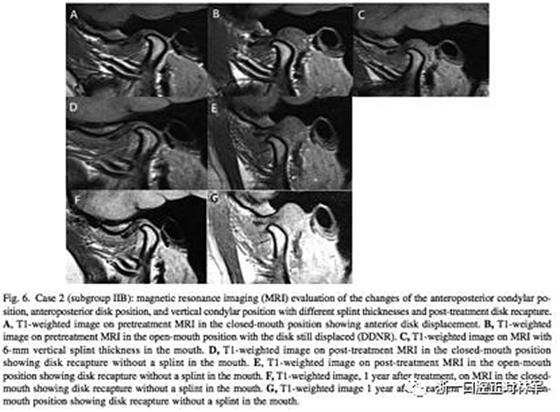

在治療12個(gè)月后,IIB組中有7例關(guān)節(jié)盤完全復(fù)位,而IIA組0例。在這7例中,張閉口位關(guān)節(jié)盤均復(fù)位的只有3例,其余4例只有在張口位時(shí)復(fù)位了(即從DDNR轉(zhuǎn)變?yōu)镈DR,分別見圖5和圖6)。再過(guò)一年后,對(duì)這7例進(jìn)行MRI研究,發(fā)現(xiàn)關(guān)節(jié)盤保持于其復(fù)位的位置。